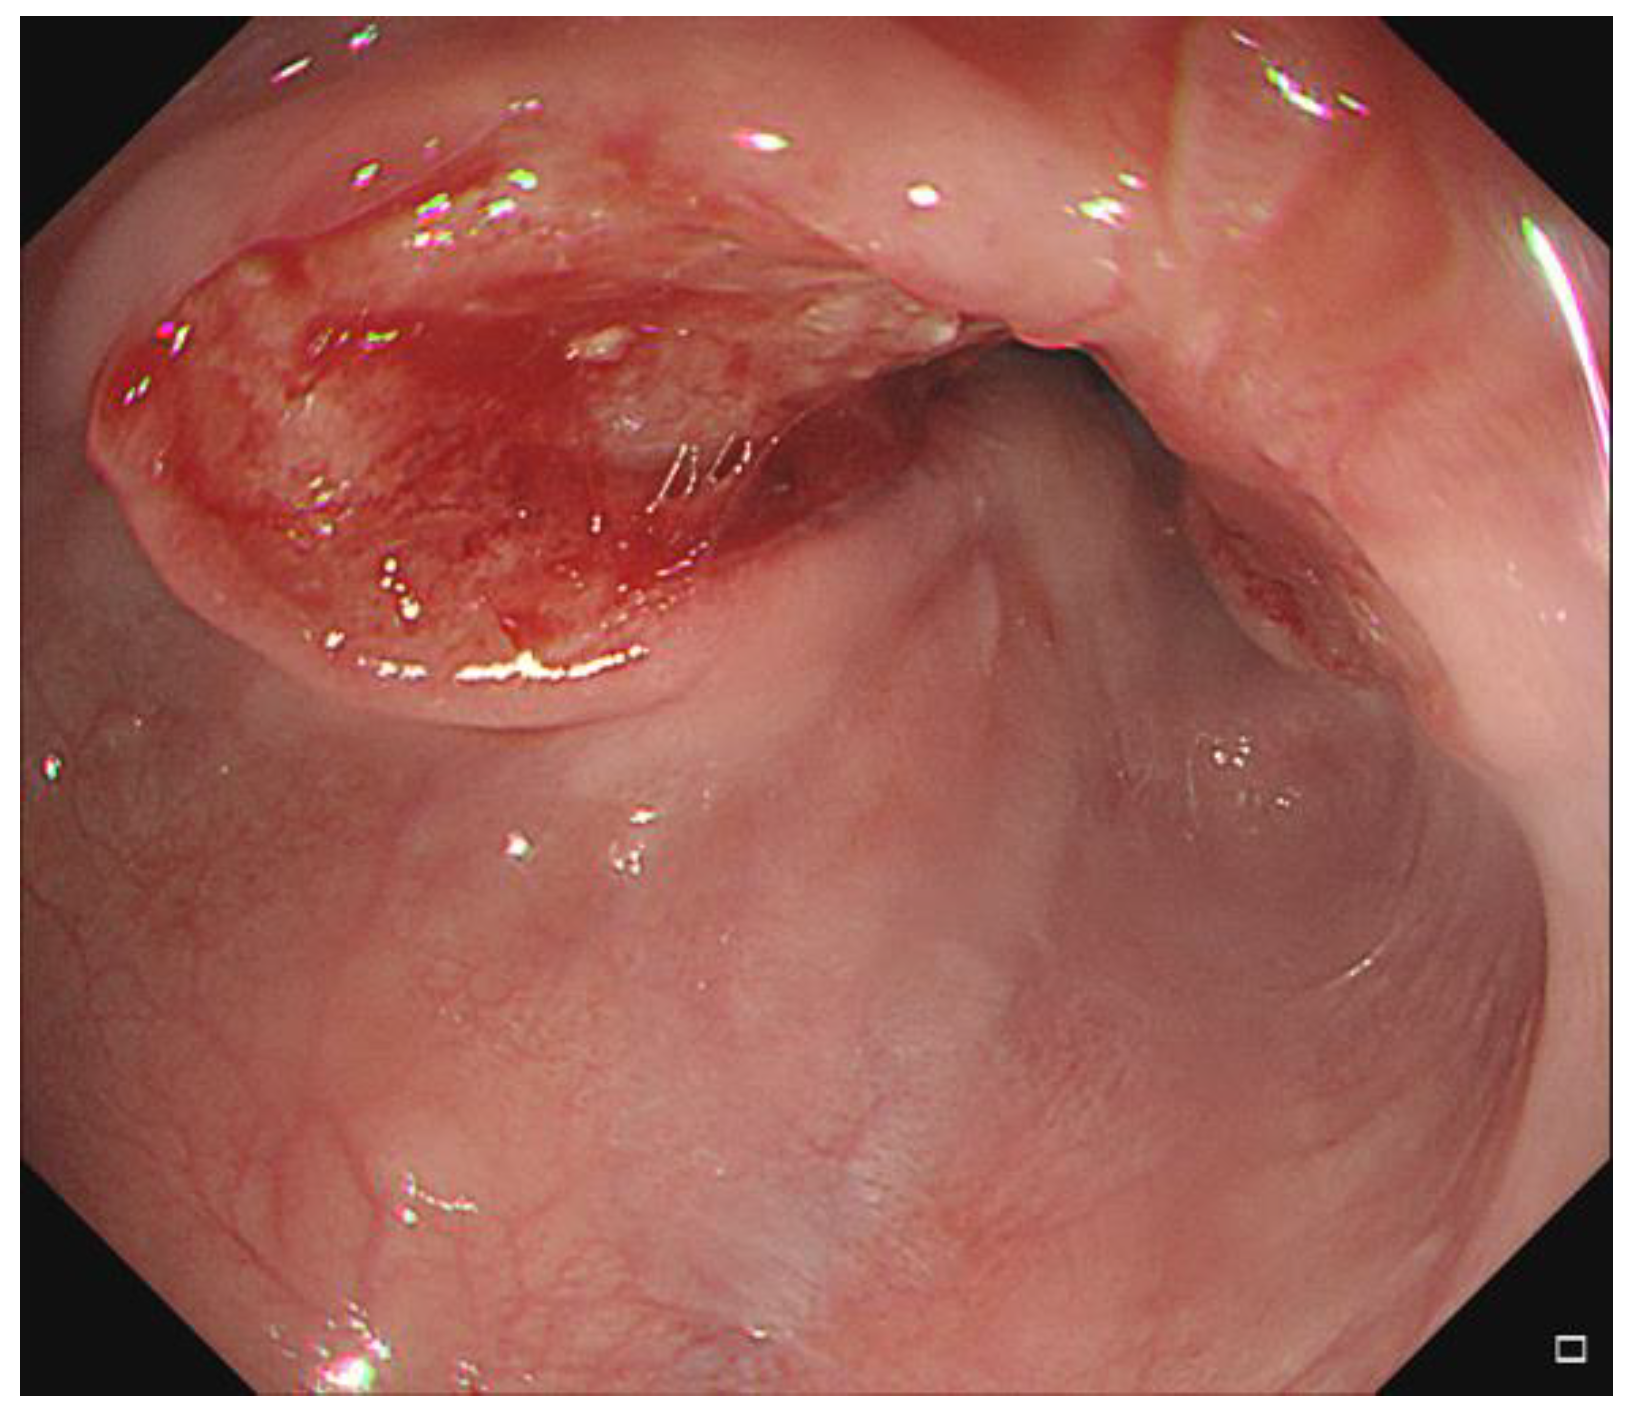

Unexpected Movement of the Esophagus across the Aorta

Choi, H.H.; Sung, S.-Y.; Ko, Y.H. Unexpected Movement of the Esophagus across the Aorta. Diagnostics 2022, 12, 1758. https://doi.org/10.3390/diagnostics12071758